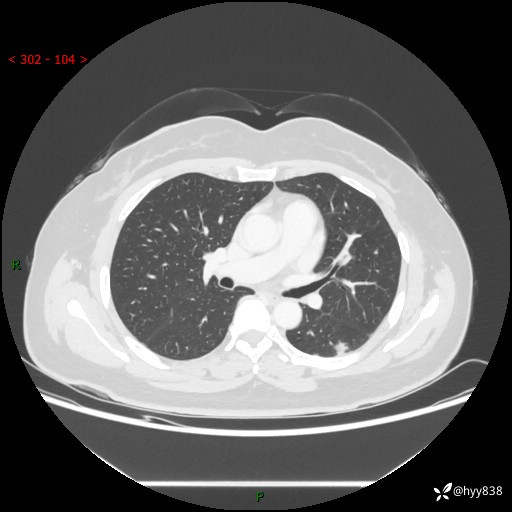

胸部CT复查+增强(2024.6)